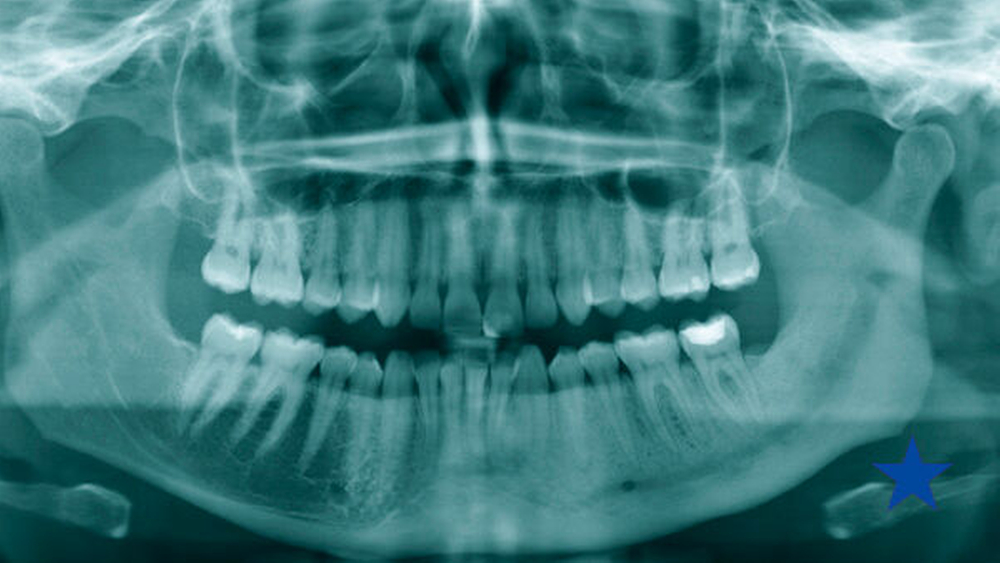

In radiologischen Untersuchungen zeigt sich bei konventionellen Röntgenaufnahmen und in der CT-Bildgebung im betroffenen Kieferareal eine vermehrte Sklerosierung des Knochens ohne Sequesterbildung (Abbildungen 1 bis 3). In der Szintigrafie des Unterkiefers zeigt sich ein chronisch entzündlicher Prozess ohne Anzeichen für eine floride bakterielle Entzündung [van Merkesteyn et al., 1988] (Abbildung 3).